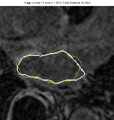

Results

The example of extracted ridges is shown in the Figure 1. The connected boundary is shown in the Figure 2. For the tested volumes, when comparing the obtained boundary with expert's manual segmentation, the average distance error is about 2 pixels. The results of GVF active contour approach are shown in the Figures 3-5. The bright gray contour is the expert's segmentation, and yellow contour is the result of our algorithm. The average distance error there is less than 2 pixels.